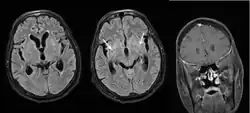

Diagnosis is by isolating Cryptococcus from a sample of affected tissue or direct observation of the fungus by using staining of body fluids.[9] It can be cultured from a cerebrospinal fluid, sputum, and skin biopsy.[9] Characteristic neuroimaging findings include dilated Virchow-Robin spaces, the ‘dirty CSF sign’,[15] hydrocephalus, cryptococcomas and hazy brain base sign. Many of these findings are non-specific, but the presence of basal meningeal enhancement is significant as it is associated with the future development of cerebral infarct. Treatment is with fluconazole or amphotericin B.[9][10]

Increased intracranial pressure is seen in about 50% of those with HIV-associated cryptococcal meningitis and is usually associated with a high fungal burden. Regular (often daily) lumbar punctures to lower the intracranial pressure by draining CSF are associated with reduced mortality in those with cryptococcal meningitis (with or without HIV).[19][49][11] But in those with suspicion of non-communicating hydrocephalus (which may present as focal neurologic symptoms or impaired mentation), a CT or MRI of the brain is required before lumbar puncture to rule out hydrocephalus, due to the risk of brain herniation with lumbar puncture. Non-communicating hydrocephalus is rare in those with HIV-associated cryptococcal meningitis.[19]